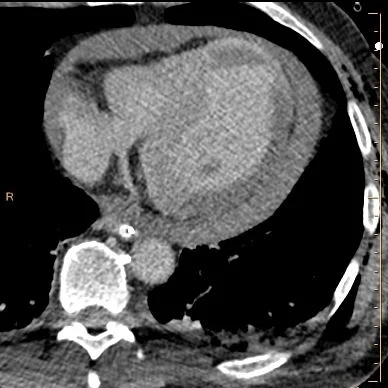

66 year old male presents awake and answering questions after MVC. FAST ultrasound shows a hemopericardium. CXR unremarkable.  Intermittently hypotensive. CPR started after pulses lost in spite of maximal resuscitation. Return of spontaneous circulation after one round of ACLS.

An EKG was done. This showed ST elevation in inferolateral leads and reciprocal elevations. Hemopericardium remained stable. A CT scan was then performed, with the suspicion of a type A dissection.

Conventional CT shows no aortic dissection. There is a large hemopericardium, as expected, and a filling defect in the LV apex consistent with thrombus. On spectral analysis, the apical clot shows no uptake of iodine. Interestingly, there is also lack of iodine uptake in the inferolateral wall, consistent with an acute MI.

Conventional trauma CT: Note hemopericardium and filling defect in the LV apex.